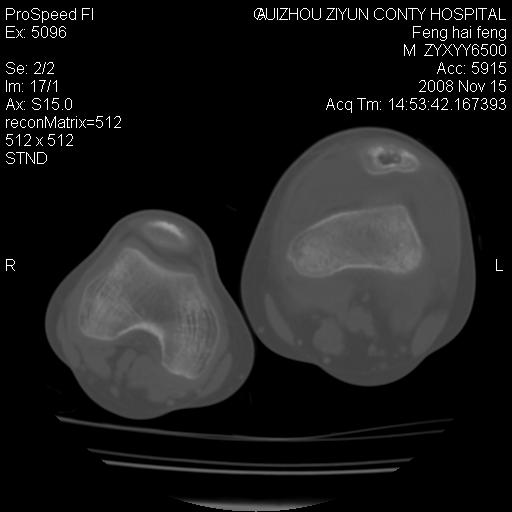

标题: CT16656:M 14Y 左膝关节肿胀一年余。其余病史不详。 [打印本页]

标题: CT16656:M 14Y 左膝关节肿胀一年余。其余病史不详。

考虑左侧髌骨结核;左膝关节滑膜肿胀、增厚,关节囊积液。

左膝滑膜型关节结核可能性大!支持!滑膜型关节结核主要ct表现:关节囊肿胀,积液,关节面见小破坏灶,并见点状死骨!

好大的左腿!考虑左侧髌骨结核,左膝关节滑膜肿胀、增厚,关节囊积液。

左侧髌骨结核;左膝关节滑膜肿胀、增厚,关节囊积液